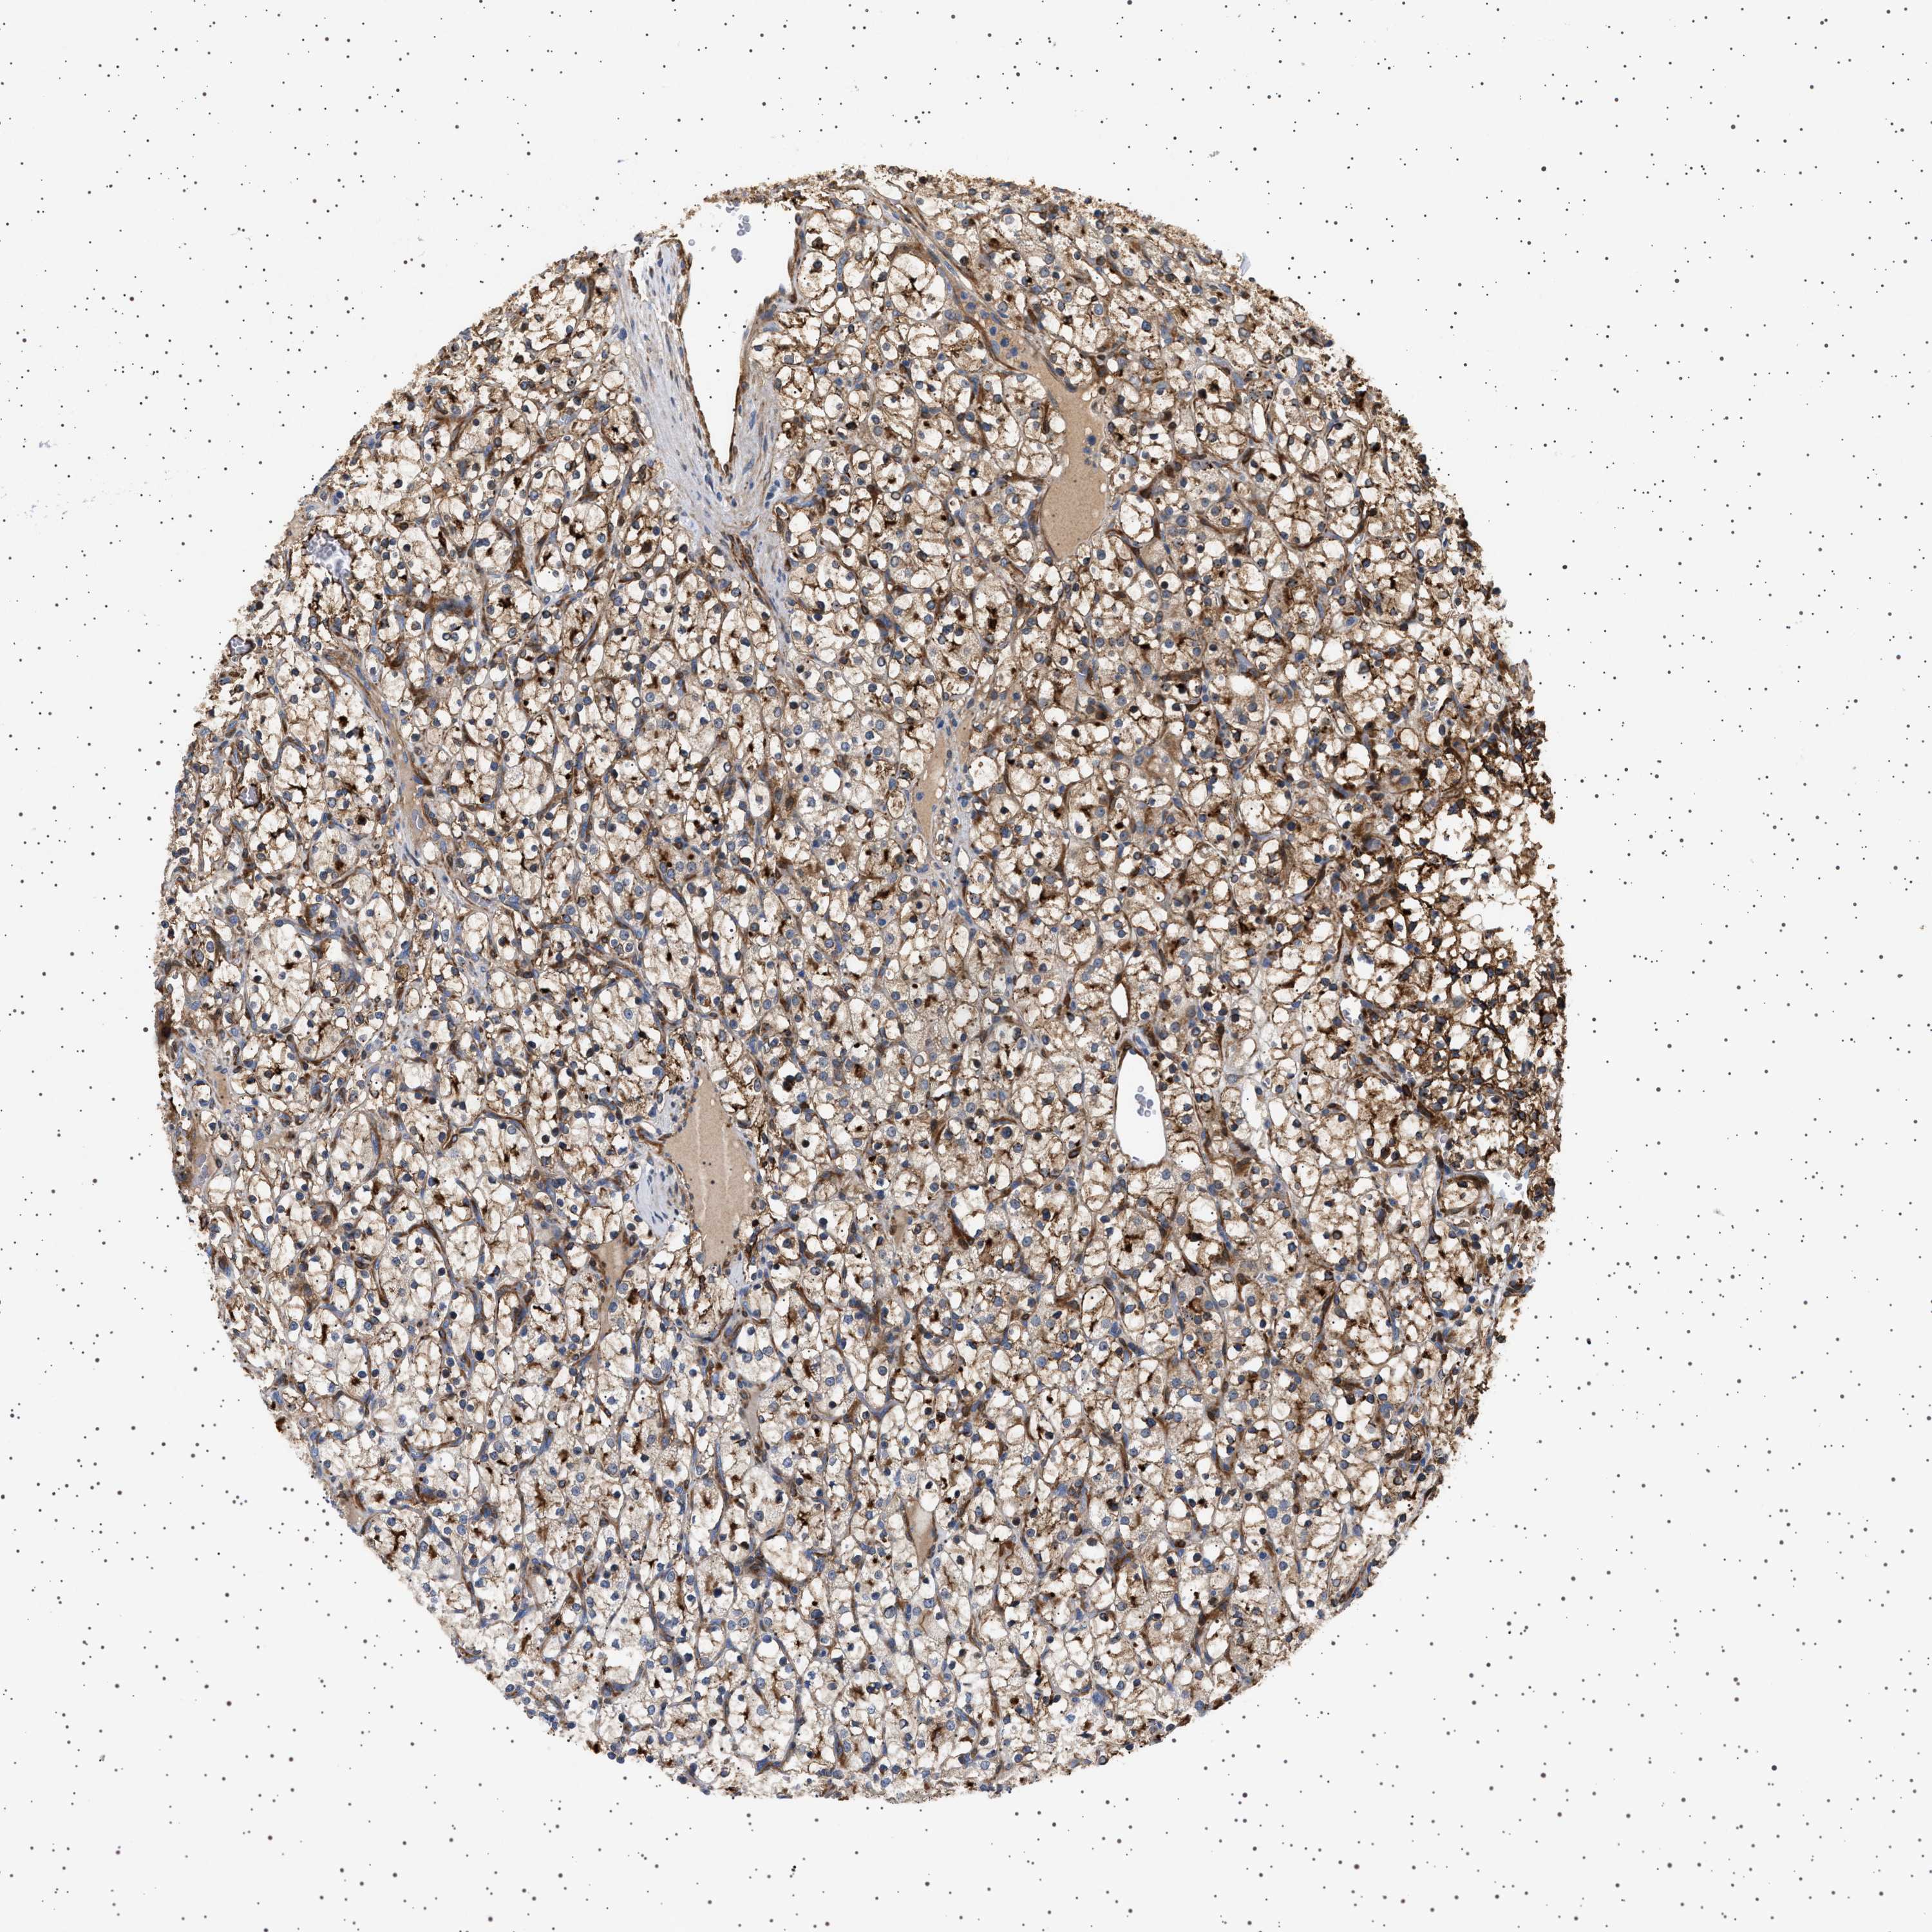

KIDNEY RENAL CLEAR CELL CARCINOMA (VALIDATION) - Interactive survival scatter ploti

The Survival Scatter plot shows the clinical status (i.e. dead or alive) for all individuals in the patient cohort, based on the same data that underlies the corresponding Kaplan-Meier plots. Patients that are alive at last time for follow-up are shown in blue and patients who have died during the study are shown in red.

The x-axis shows the expression levels (FPKM) of the investigated gene in the tumor tissue at the time of diagnosis. The y-axis shows the follow-up time after diagnosis (years). Both axes are complimented with kernel density curves demonstrating the data density over the axes. The top density plot shows the expression levels (FPKM) distribution among dead (red) and alive patients (blue). The right density plot shows the data density of the survived years of dead patients with high and low expression levels respectively, stratified using the cutoff indicated by the vertical dashed line through the Survival Scatter plot. This cutoff is automatically defined based on the FPKM cutoff that minimizes the p-score. The cutoff can be changed by dragging the vertical line or by entering a cutoff value in the square labeled "Current cut-off".

Under the Survival Scatter plot the p-score landscape (black curve; left axis) is shown together with dead median separation (red curve; right axis). Dead median separation is the difference in median mRNA expression between patients who have died with high and low expression, respectively. It is calculated as follows: median FPKM expression of dead patients with high expression - median FPKM expression of dead patients with low expression. This is intended to aid the user in visually exploring custom cutoffs and the associated p-scores and dead median separation.

Individual patient data is displayed and can be filtered by clicking on one or more of the category buttons on the top of the page. Categories describing expression level and patient information include: high, low, alive, dead, female, male and tumor stages. The scale of the x-axis can be toggled between linear and log-scale by clicking on the "x log" button. Mouse-over function shows TCGA ID, patient information and mRNA expression (FPKM) for each patient.

& Survival analysisi

Kaplan-Meier plots summarize results from analysis of correlation between mRNA expression level and patient survival. Patients were divided based on level of expression into one of the two groups "low" (under cut off) or "high" (over cut off). X-axis shows time for survival (years) and y-axis shows the probability of survival, where 1.0 corresponds to 100 percent.

GUCY1B1 is validated prognostic, high expression is favorable in Kidney Renal Clear Cell Carcinoma (validation)

Best expression cut offi

: 25.56

P scorei

5-year survival highi

5-year survival lowi

TCGA RNA samplesi

Average pTPM 33.1

Number of samples 100